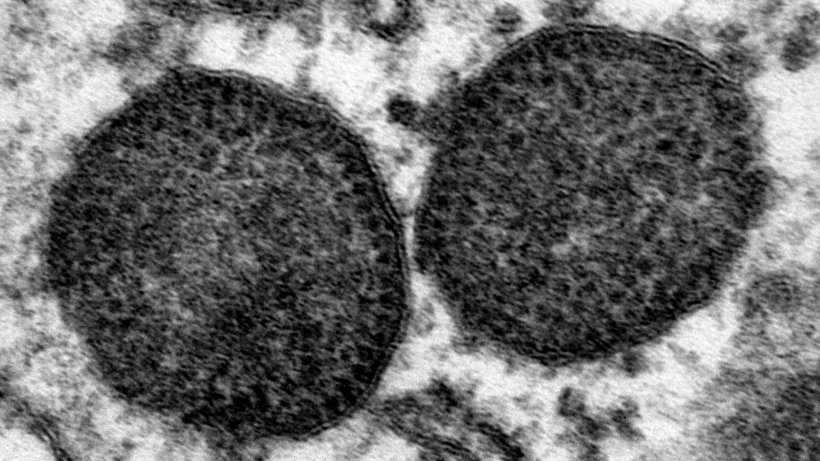

Ocena powiązań filogenetycznych szczepów PCV2, porównanie i analiza 1680 sekwencji otwartej ramki odczytu 2 (ORF2) PCV2 z zastosowaniem różnych metod statystycznych.

Do analizy filogenetycznej PCV2 wykorzystano 1537 sekwencje genów ORF2 PCV2, które zostały opublikowane przed lutym 2014 r. w "GenBank", globalnej bazie danych genomowych oraz 143 dodatkowych sekwencji ORF2 z bazy danych Laboratorium Diagnostycznego Iowa State University (tj. łącznie 1680 sekwencji ORF2).

Badanie potwierdziło, że PCV2 można podzielić na 4 główne podtypy: PCV2a, PCV2b, PCV2c i PCV2d. Ponadto autorzy opisują 6 mniejszych pośrednich kladów mieszczących się między tymi podtypami. Jeden z nich wydaje się być ograniczony tylko do Azji. Jednakże szczepy tego kladu są raportowane na bieżąco, co sugeruje, że może jest on aktywny. Pozostałe pośrednie klady obejmują jedynie bardzo ograniczoną liczbę szczepów, dlatego mogą być uważane za nieaktywne. Mogą odpowiadać małym wygaszonym grupom wykazującym mniejszą aktywnosć: pośrednie, ewolujące szczepy wirusa; lub artefakty testu. PCV2c wydaje się być wymarłą grupą wirusów. Przynależność poszczególnych szczepów do różnych genotypów i kladów pośrednich czasami zależy od zastosowanego modelu statystycznego i od liczby szczepów odniesienia stosowanych do analizy.

Wyniki potwierdziły ponadto, że były dwie ważne zmiany z jednego podtypu do innego: w 2003 r. przed stosowaniem szczepionek PCV2, z PCV2a do PCV2b, a druga zmiana dotyczyła PCV2b do PCV2d, na przykład w USA głównie od 2011 do 2014 roku.

Dalsze badanie filogenetyczne sugeruje, że PCV2b i PCV2d ewoluowały niezależnie od siebie przez ponad 20 lat. Ponadto w każdym podtypie występuje ciągła rozbieżność genetyczna. Powód tego, że PCV2 ma wysoką szybkość mutacji, a także tak wysoką różnorodność genetyczną - nietypową dla wirusów DNA - nie jest znany. Nie jest znana przyczyna ciągłego pojawiania się szczepów i zmian genotypowych, które zostały zaobserwowane. Pierwsza zmiana miała miejsce przed wprowadzeniem szczepionek PCV2.

Badanie to wykazuje, że PCV2 ewoluuje znacznie szybciej niż inne wirusy DNA, a jego różnorodność jest szersza. Branża trzody chlewnej powinna nadal monitorować ewolucję PCV i określić jego znaczenie dla kontroli PCVD.